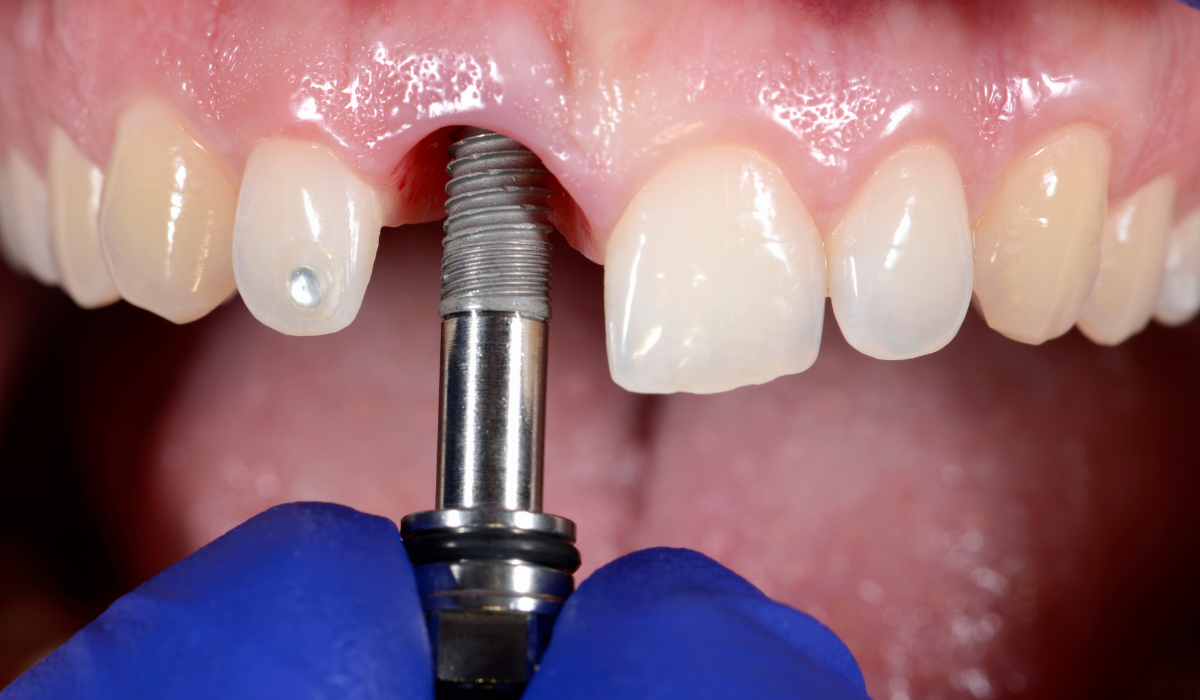

- 임플란트 시술: 승인 후 임플란트 시술 진행

임플란트 시술 전, 전신 건강 상태 와 구강 상태 를 꼼꼼하게 확인해야 합니다. 특히, 당뇨병, 고혈압, 골다공증 등의 질환이 있는 경우 의사와 상담 하는 것이 중요합니다.

구강 건강 상태 확인

- 잇몸 염증 여부 확인

- 잇몸 뼈 상태 확인